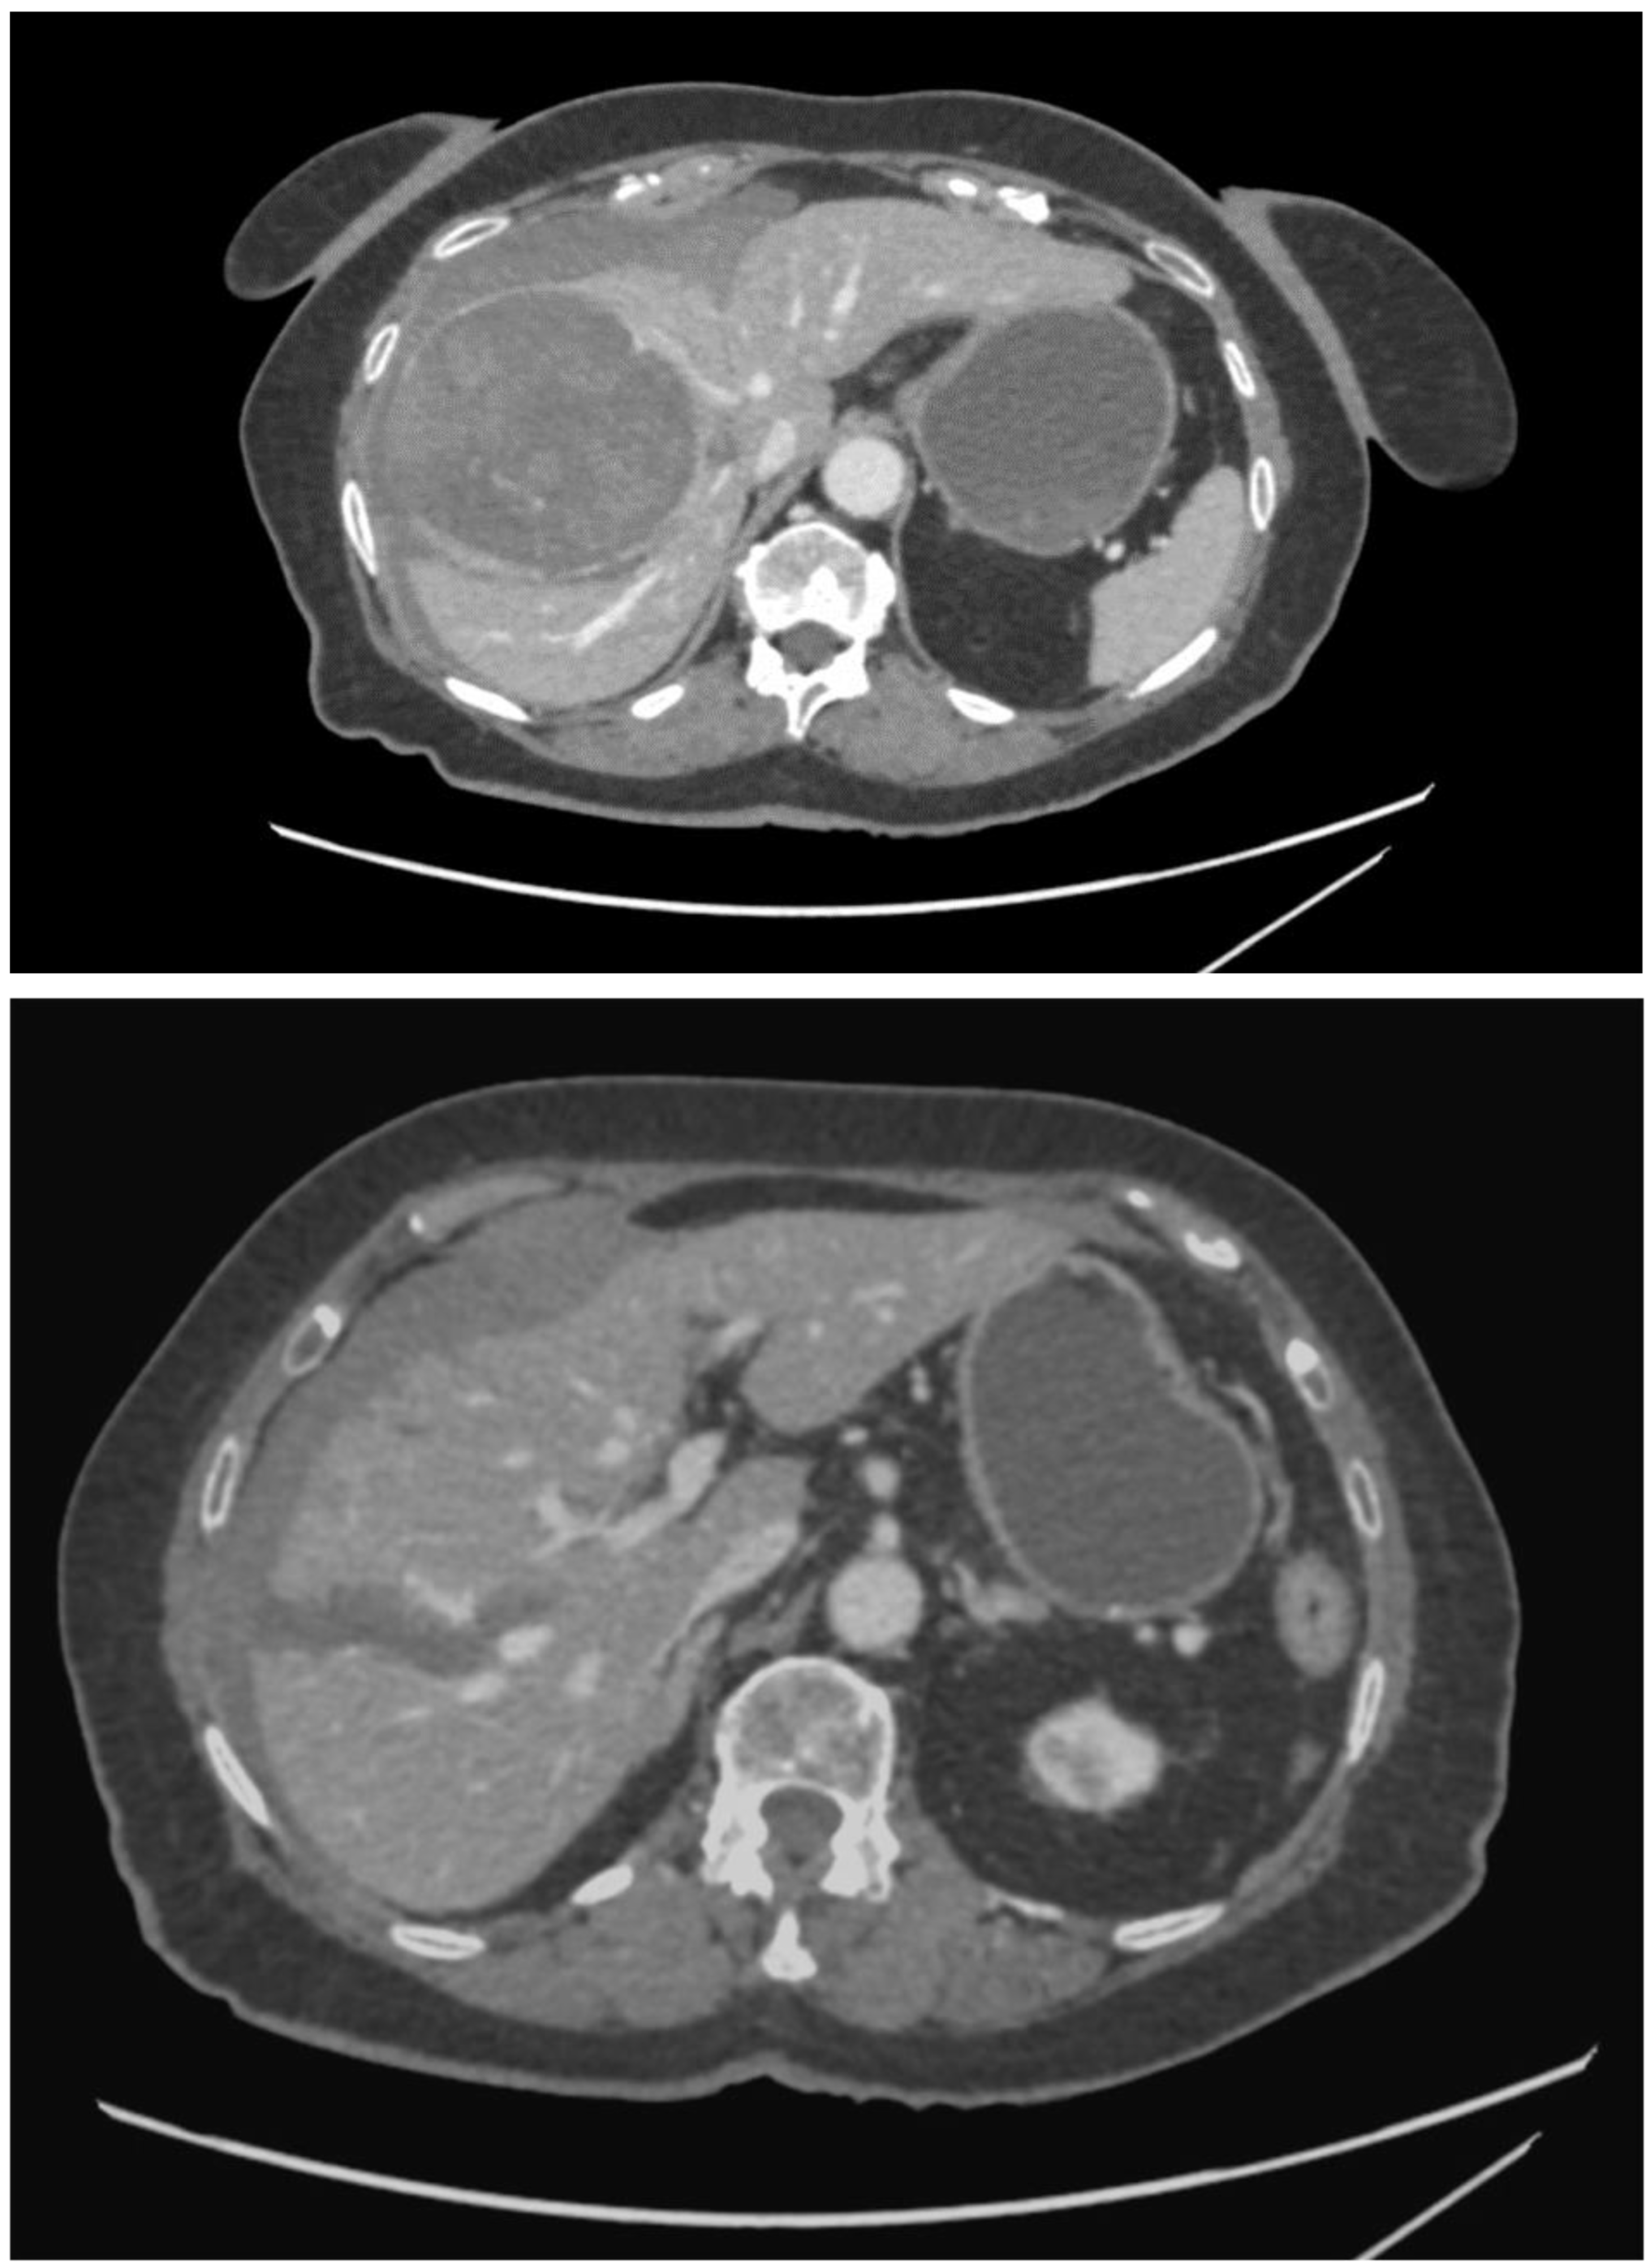

2. Case Report